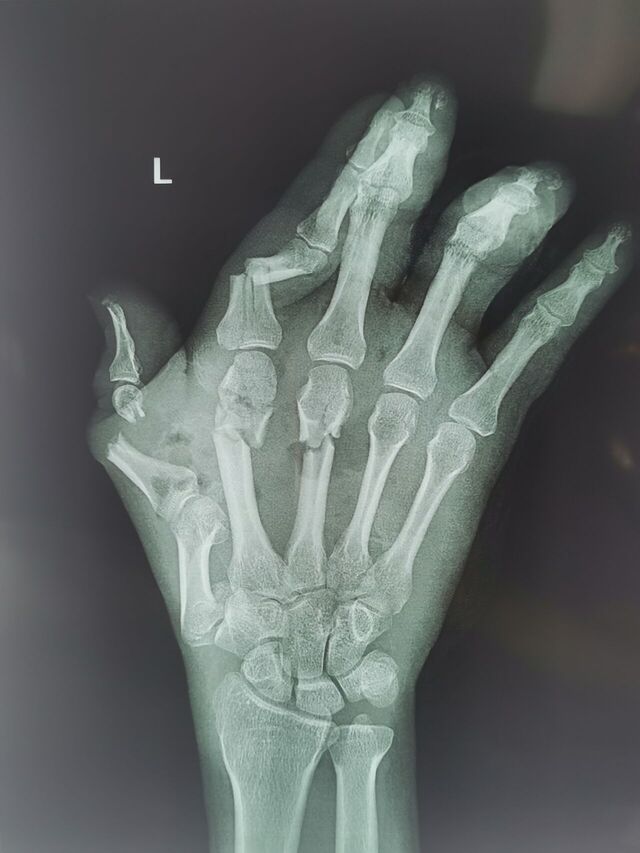

拇指先天畸形

mmexport1754487711297.jpg

mmexport1754487742008.jpg